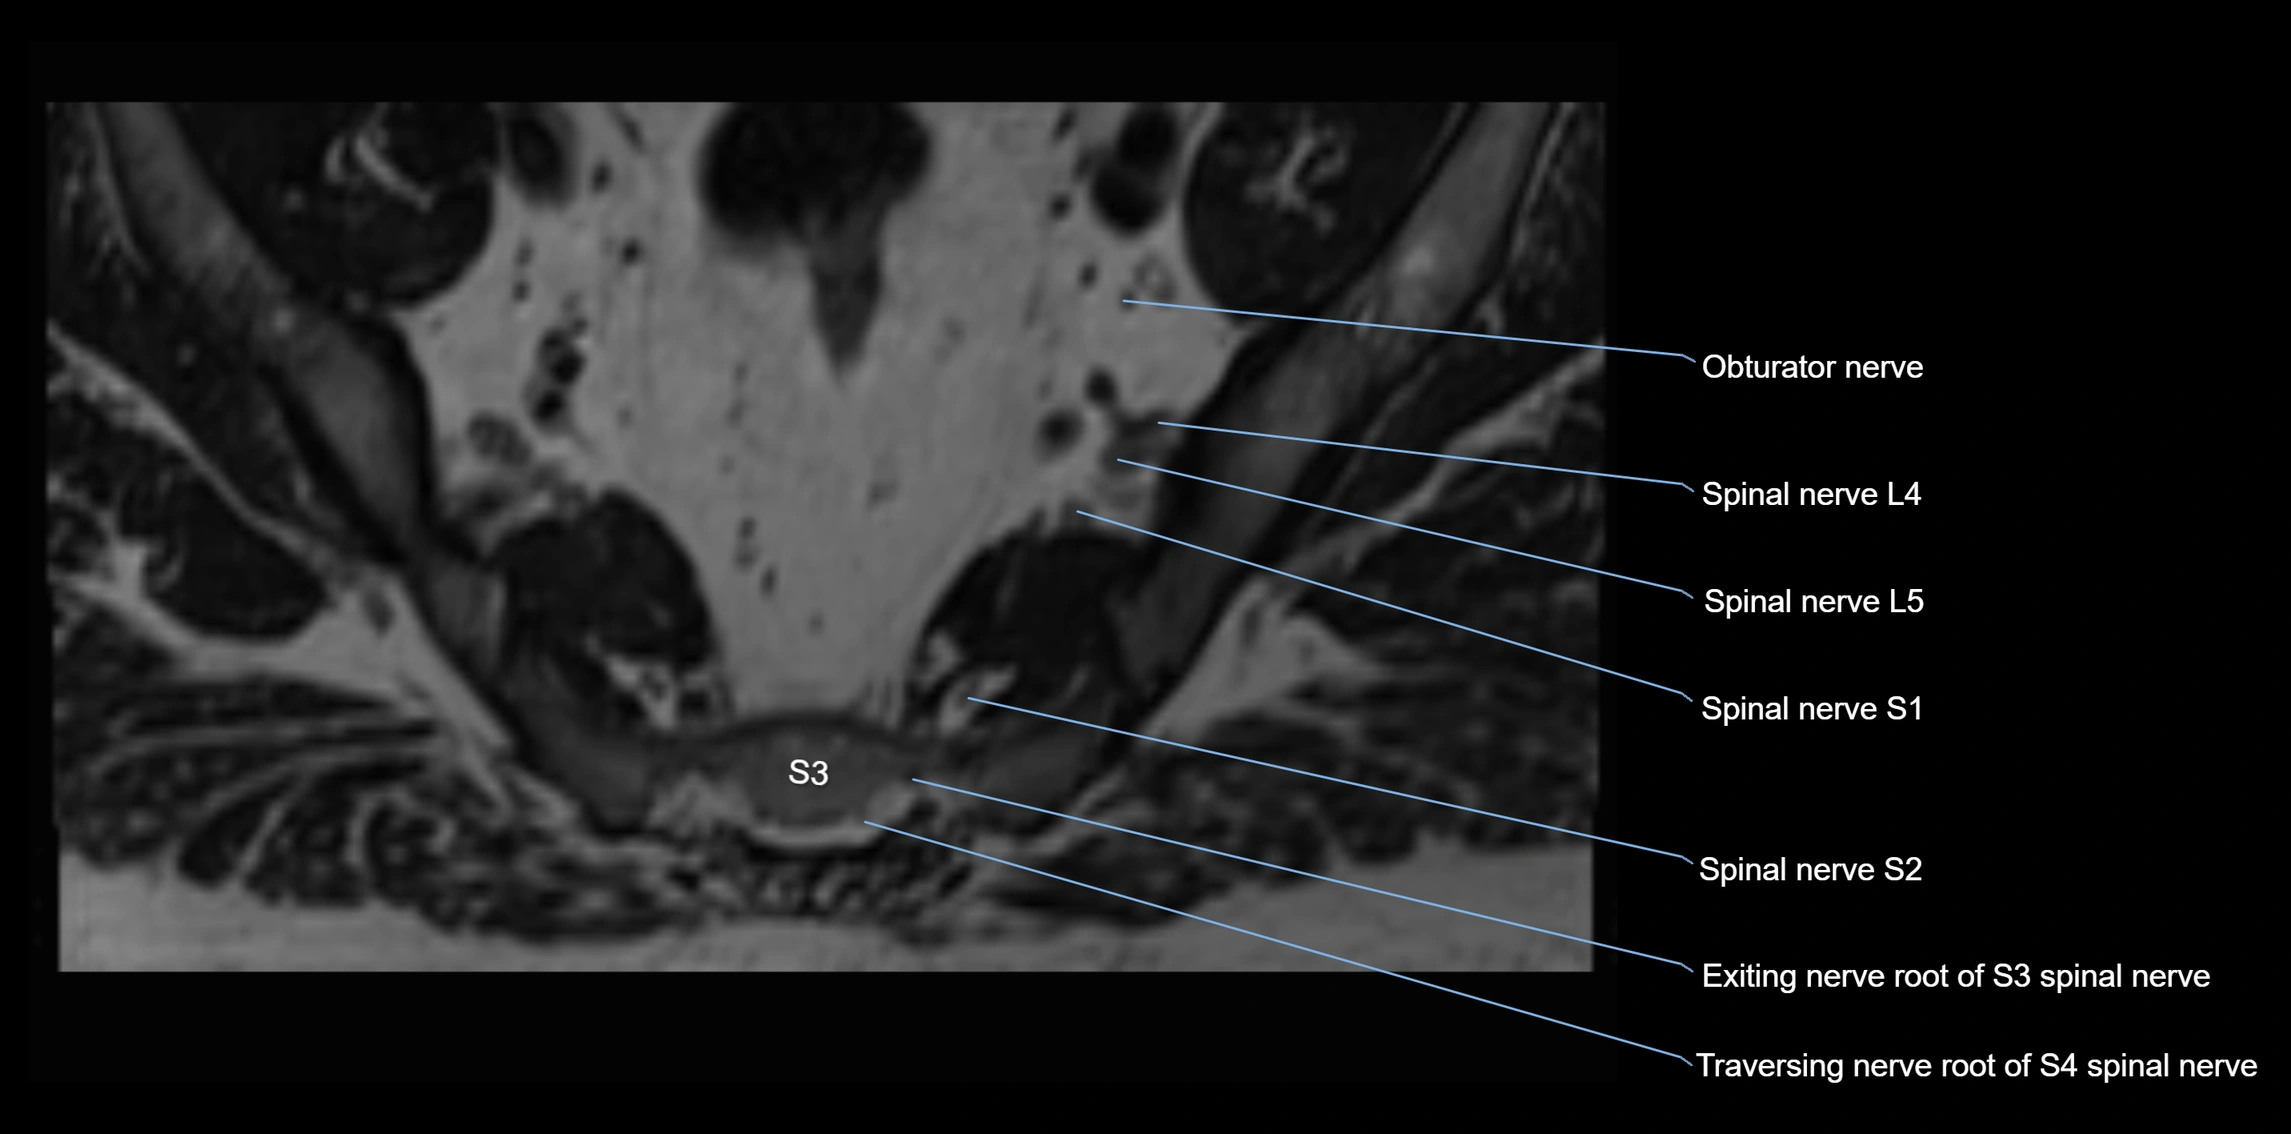

MRI Appearance

T1-weighted images:

• Nerve appears as a very thin low-to-intermediate signal intensity structure

• Surrounded by bright fat, aiding visualization

T2-weighted images:

• Nerve shows intermediate to mildly hyperintense signal compared to muscle

• Pathological involvement appears brighter

STIR (Short Tau Inversion Recovery):

• Normal nerve appears dark

• Inflamed or entrapped nerve appears bright hyperintense

T1 Fat-Sat Post-Contrast:

• Normal nerve enhances minimally

• Pathologic nerve (neuritis, entrapment, tumor infiltration) shows focal or diffuse enhancement

3D T2 SPACE / CISS:

• Nerve appears intermediate to mildly hyperintense compared to muscle

• Surrounded by bright fat or CSF, improving visualization

• Best sequence for mapping small pelvic nerves such as the anococcygeal